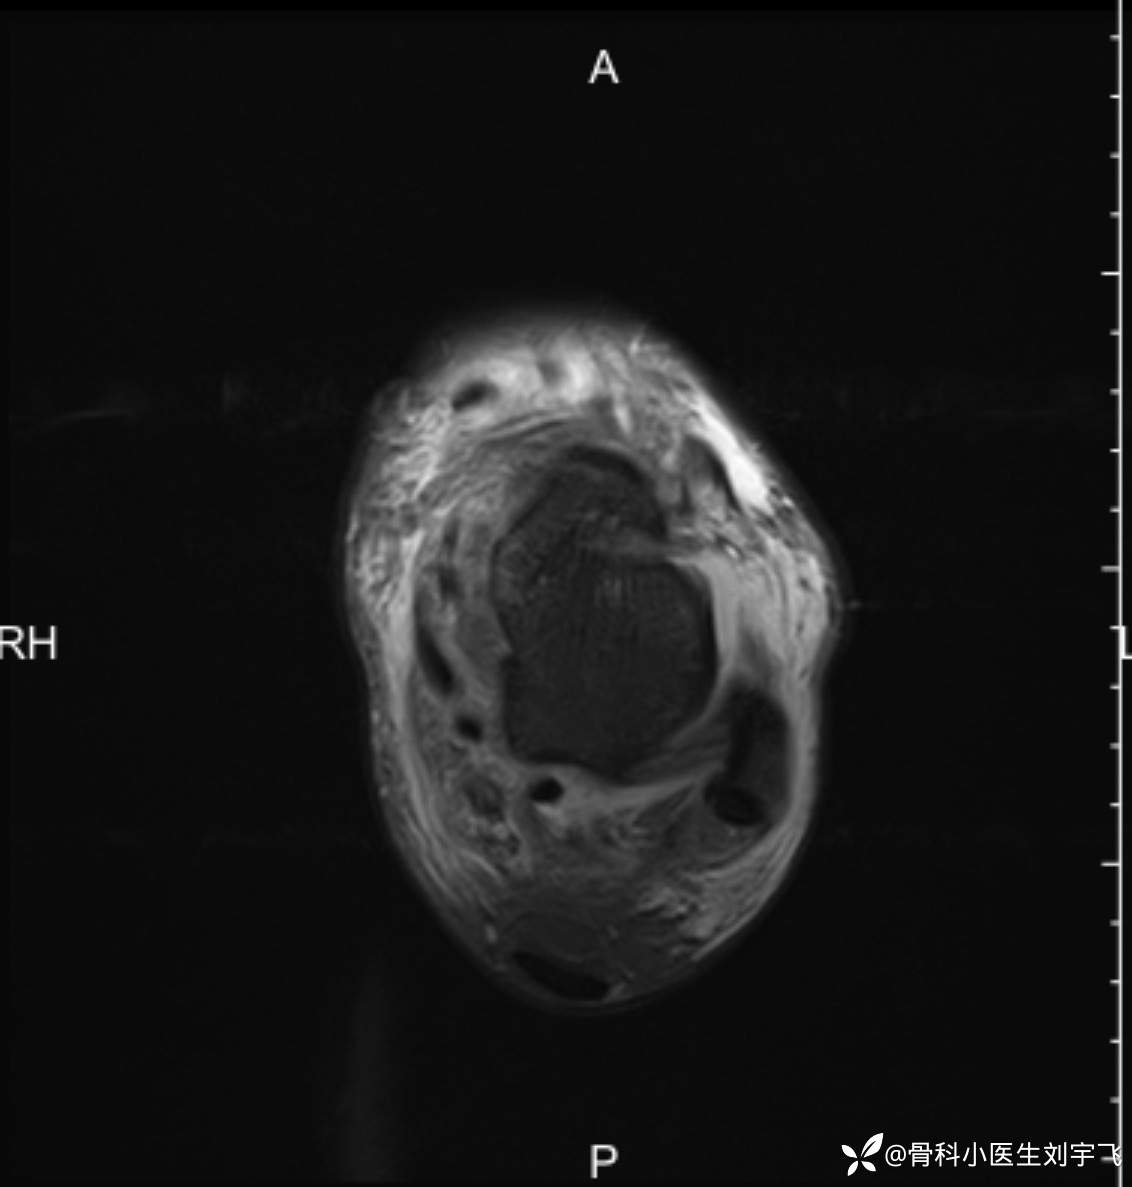

踝关节扭伤后,内外侧疼的很厉害,大家看一下这个核磁

辅助检查:MRI X线

临床诊断:距腓前韧带撕裂 三角韧带损伤、胫骨前肌腱损伤?